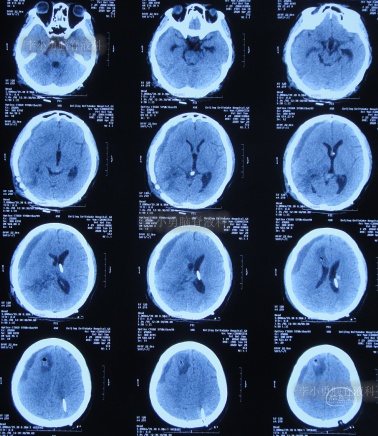

图-4:2006年8月23日头颅CT

第1次脑室腹腔分流术后8个月即2007年5月1日,再次出现头晕头痛,在江苏省江阴市某医院查头颅CT(图-5)后传给给予手术医生,医生考虑是分流管堵塞。

图-5:2007年5月1日头颅CT

因分流管堵塞,2007年5月2日(第1次脑室腹腔分流术后8个月),第2次住入给予手术的医院,2007年5月5日(入院后3天),术后例行查头颅CT(图-6)后,加做了脑室腹腔分流术,但保留了原脑室分流管。

图-6:2007年5月5日头颅CT

图-7:2007年5月6日头颅CT上海

第2次脑室腹腔分流术后3月余即2007年8月15日,查头颅CT示未见异常(图-8)。

图-8:2007年8月15日头颅CT